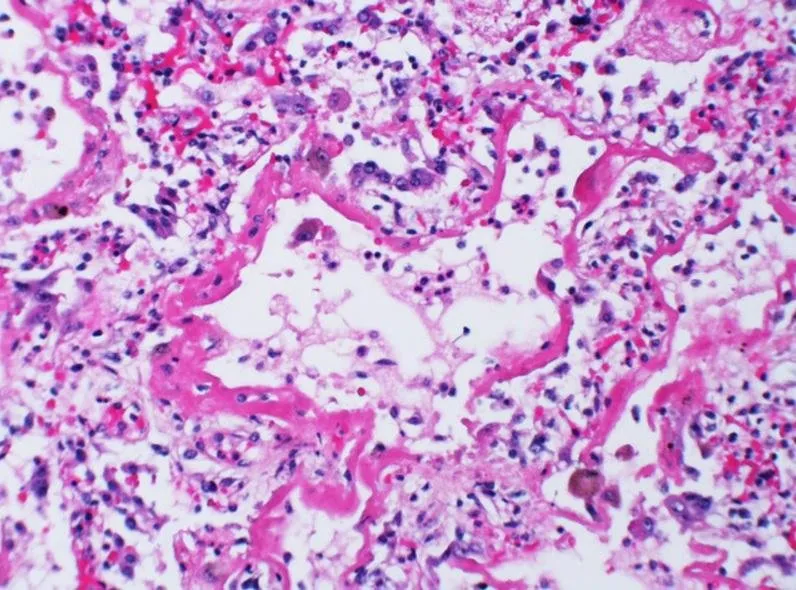

Ryc. A – biopsja płuca u pacjenta z ARDS, która pokazuje, że przestrzenie, które powinny być wykorzystywane do wentylacji są wyłączone z tego procesu przez zalegający płyn – obrzęk.

Preparat histologiczny płuca

Ryc. B – na tym preparacie uwidoczniono tworzenie się błon hialinowych, obrzęk i napływ komórek stanu zapalnego. Utworzenie się błon szklistych dodatkowo zwiększa grubość bariery dyfuzyjnej, co utrudnia prowadzenie wymiany gazowej, a w konsekwencji napędza niepożądaną kaskadę zdarzeń.